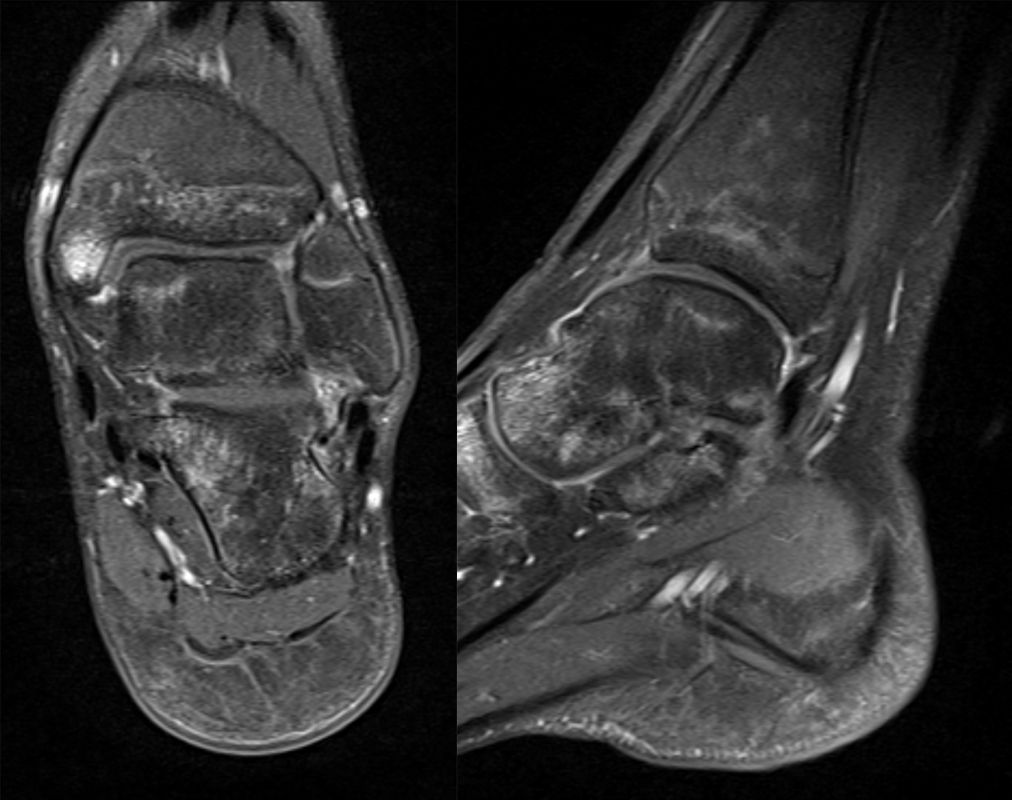

Die Kernspintomographie hat ihre Stärke in der Darstellung von Weichteilverletzungen. Insbesondere Verletzungen der Wachstumsfuge, des Periosts und der Bänder lassen sich gut visualisieren. Nachteilig ist die Untersuchungsdauer von 20-30 Minuten. Bleibt das Kind während dieser Zeit nicht ruhig liegen, kommt es zu Bewegungsartefakten, welche die Beurteilbarkeit der Bilder beeinträchtigen.

Fugengelenkfrakturen treten typischerweise vor dem 10. Lebensjahr auf, in einer Phase, in welcher die Wachstumsfugen noch weit offen sind. Dieser Frakturtyp betrifft fast ausschließlich den medialen Malleolus. Laterale Frakturen sind extrem selten, teilweise kommt es zu lateralen Bandverletzungen oder Fugenschaftfrakturen der distalen Fibula. Die Frakturlinie verläuft in einer Verlängerungslinie von der medialen Taluskante nach proximal. Häufig stellen sich Verletzungen des Innenknöchels im Röntgenbild schlechter dar, insbesondere wenn die Aufnahmen verdreht sind oder die Ebene der Fraktur bei geringer Dislokation verkippt zur Röntgenebene liegt. Besteht klinisch der geringste Hinweis auf eine Verletzung des Innenknöchels, muss aufgrund der Tragweite der Verletzung durch entsprechende Aufnahmen gegebenenfalls auch Schnittbildverfahren die Verletzung sicher diagnostiziert oder ausgeschlossen werden (Abb. 15).

Bei kindlichen Verletzungen des medialen Malleolus handelt es sich nach L. v. Laer um eine sogenannte Kadiläsion, d.h. eine Verletzung mit hohem Risiko eines schlechten Behandlungsergebnisses bei nicht korrekter Behandlung. Selbst bei optimaler Therapie ist das Risiko für spätere Wachstumsstörungen hoch, sodass diese Verletzungen nicht selten ein juristisches Nachspiel haben. Durch die Verletzung der wachstumsaktiven Zone kann es zu einem vorzeitigen Verschluss der Wachstumsfuge kommen, mit entsprechendem Fehlwachstum. Das Risiko eines vorzeitigen Verschlusses der Wachstumsfuge korreliert mit dem Ausmaß der Schädigung der wachstumsaktiven Zone. Ab dem 13. Lebensjahr wird das Risiko bei reduzierter Wachstumsaktivität zunehmend geringer.

Fugengelenkfrakturen können die Wachstumsfuge durchkreuzen (Abbildung 16a), ohne oder nur mit minimaler Beteiligung der Fuge sehr weit medial liegen (Abbildung 16b) oder durch die Fuge auslaufen (Abbildung 16c). Relevant für die Wachstumsprognose ist weniger die Form der Fraktur, sondern das Alter des Patienten zum Zeitpunkt des Traumas sowie das Ausmaß der Schädigung der Wachstumsfuge, wobei eine Korrelation mit dem Ausmaß der Dislokation besteht.